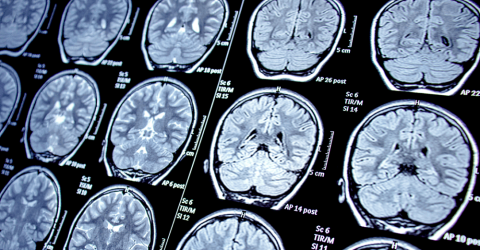

Quase metade da população mundial em 2021 sofria de uma doença neurológica, principal causa de problemas de saúde e incapacidade a nível global, estima um estudo hoje publicado na revista médica The Lancet Neurology.

De acordo com o estudo, 3,4 mil milhões de pessoas no mundo eram afetadas em 2021 por uma doença neurológica, com o Acidente Vascular Cerebral (AVC), a encefalopatia neonatal, a enxaqueca, a doença de Alzheimer e outras demências, a neuropatia diabética, a meningite, a epilepsia e o cancro a serem os maiores responsáveis pela perda de saúde ao nível do sistema nervoso.

O estudo, que avaliou o peso das doenças, lesões e fatores de risco, salienta que o número de pessoas que viveram ou morreram entre 1990 e 2021 com patologias neurológicas, como AVC, doença de Alzheimer e outras demências ou meningite, cresceu substancialmente devido não só ao aumento e envelhecimento da população, mas também devido ao “aumento da exposição a fatores de risco ambientais, metabólicos e de estilos de vida”.

Em 2021, as cefaleias de tensão e as enxaquecas afetavam, juntas, cerca de 3,1 mil milhões de pessoas à escala global, segundo as estimativas plasmadas no trabalho publicado pela The Lancet Neurology, que realça que a neuropatia diabética foi a doença neurológica que mais cresceu de 1990 a 2021, tendo os casos mais do que triplicado, atingindo 206 milhões de pessoas no mundo há três anos.

O estudo concluiu que em 2021 as patologias neurológicas foram as principais responsáveis pelo peso das doenças à escala global, à frente das doenças cardiovasculares, devido aos anos de perda de vida saudável por doença, incapacidade ou morte prematura.